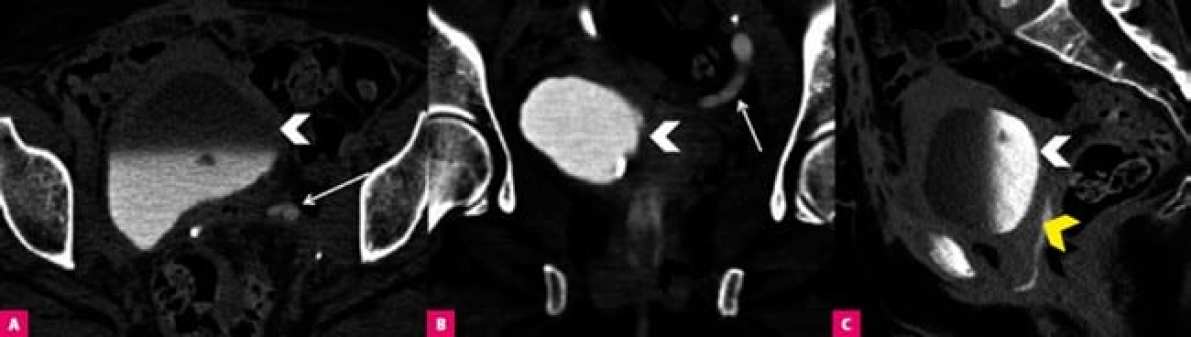

Уретеро-вагинальный свищ у женщины после операции по поводу рака шейки матки. КТ-изображения в осевой (A), фронтальной (B) и сагиттальной (C) плоскостях показывают контрастную мочу в мочевом пузыре (белая стрелка) и заполненную контрастом полость между мочеточником и влагалищем (желтая стрелка), вкупе с расширением левого мочеточника (стрелка)